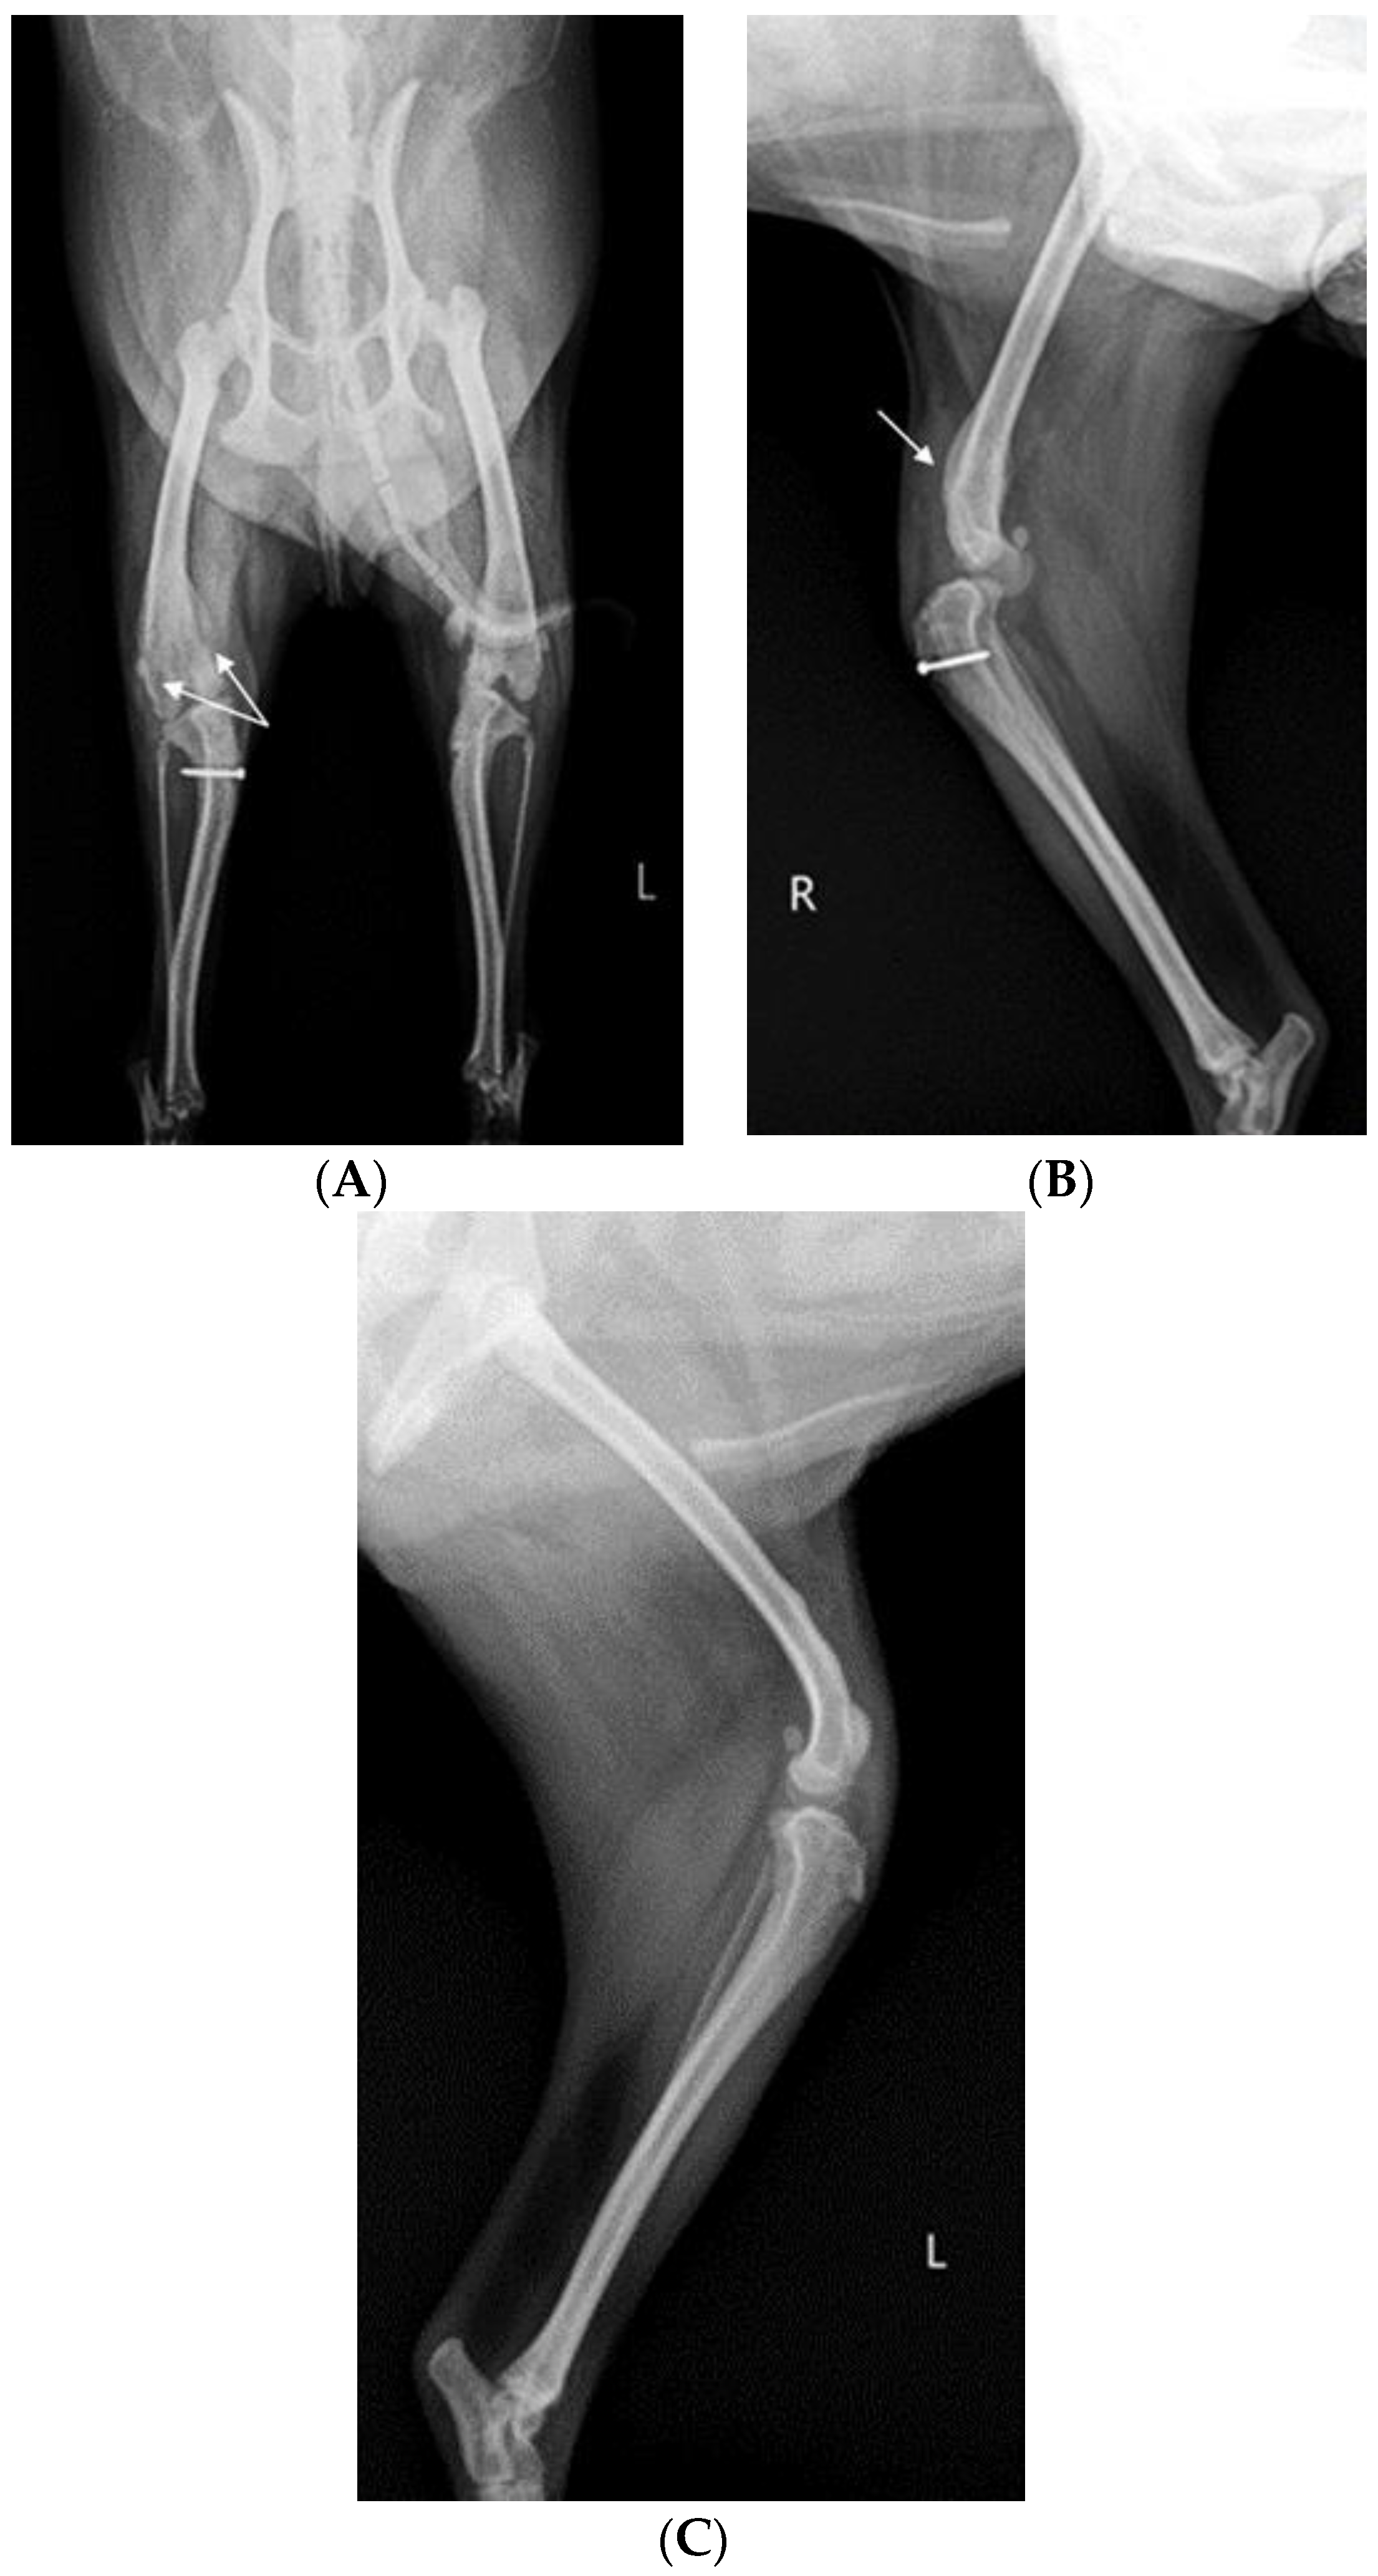

X-ray (E7239X, TOSHIBA, Tokyo, Japan) analysis was conducted. According to radiograph imaging (Weview pacs system, Seoul, Republic of Korea), the screw fixing the bone fragment to the tibial tubercle in the right hind limb had remained, and the patella was not recognized in the radiography view, which was consistent with the results following palpation (Figure 1A,B). Bone proliferation was noted, and edema was observed around the stifle joint (Figure 1A,B). Severe MPL, periostitis, and edema around the stifle joint in the left hind limb were observed (Figure 1A,C). Following a physical examination, complete blood count (Procyte Dx analyzer, Maine, USA) and biochemistry device (Catalyst One chemistry analyzer, Maine, USA) were measured. Neutrophil levels were observed to be slightly increased, namely, 11.71 μL (78.2%), suggesting that inflammatory responses were in progress (Table 1).

Figure 1.

A 2-year-old Pomeranian dog with chronic weight-bearing lameness of the stifle joints in both hind limbs. (A) Craniocaudal radiographic views of the stifle joints of the dog. (B) Lateral radiographic views of the right stifle joints. (C) Medial radiographic views of the left stifle joints. a: osteophyte, b: periostitis, c: residual screw for tibial tuberosity transposition, d: periostitis, R: right, and L: left.